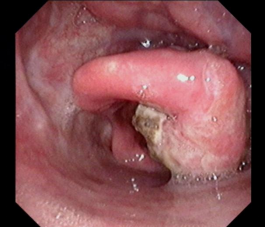

喉癌颈淋巴结转移

声门型喉癌不易发生颈淋巴结转移,声门上型及声门下型则易发生颈淋巴结转移。